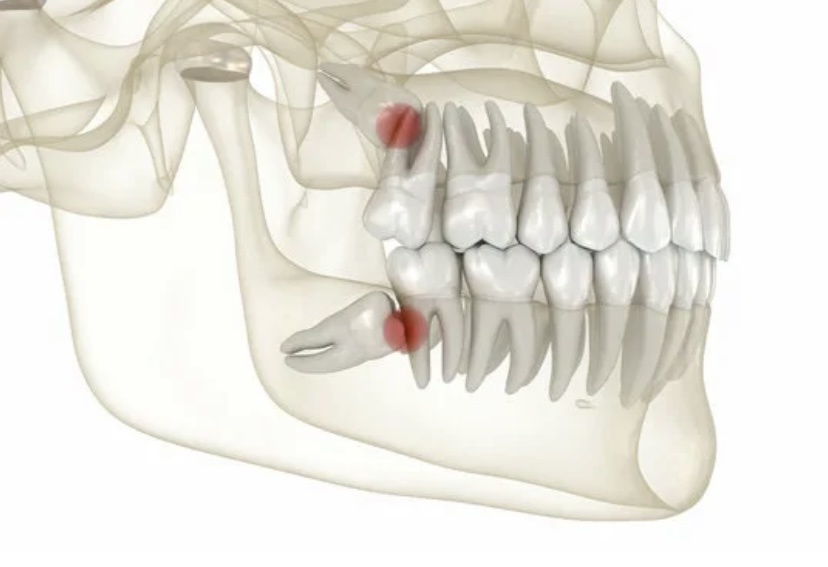

Статистика показывает, что у 65–70 % людей третьи моляры прорезываются с осложнениями. Более половины проблем связаны с недостатком места в зубном ряду. Это приводит к ретенции — состоянию, при котором зуб остается частично или полностью в костной ткани.

Примерно у 20 % людей третьи моляры растут под неправильным углом, повреждают соседние зубы и десны.

Из-за этого пациенты испытывают боль, а ткани ротовой полости воспаляются.

Удаление необходимо, если зуб частично прорезался и травмирует соседние ткани. Также удаление требуется, если зуб расположен под неправильным углом, давит на соседние зубы или разрушен кариесом.

Непрорезавшиеся зубы, которые остаются внутри челюсти, также могут быть причиной беспокойства. Если такие зубы расположены под углом или давят на соседние, это может привести к смещению зубного ряда или другим осложнениям.